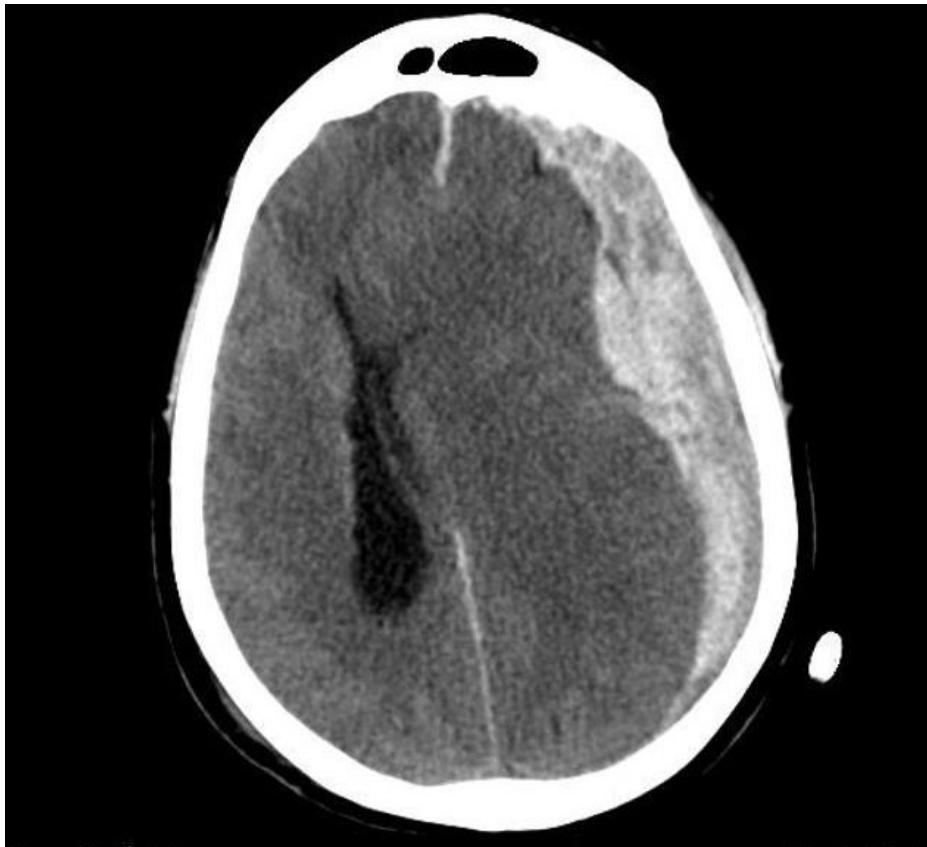

Subdural Hematoma

- Diagnosis: Subdural Hematoma.

- CT Finding: Crescent (Sickle-shaped) hyperdensity; can cross suture lines.

- Pathology: Bleeding from bridging veins.

- Note: Higher density indicates acute bleeding.